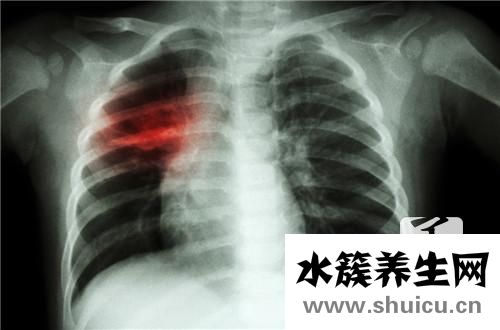

2、心臟層面病癥造成左后背疼痛

并且肺臟、心臟層面等病癥,也是造成左后背疼痛的元兇。當背部疼痛主要表現比較輕度時,病人經常會忽略它的存有??墒?病癥發展趨勢到情況嚴重的水平,就需要認真完成,如腰椎的創傷骨折、結核病、腫瘤等。